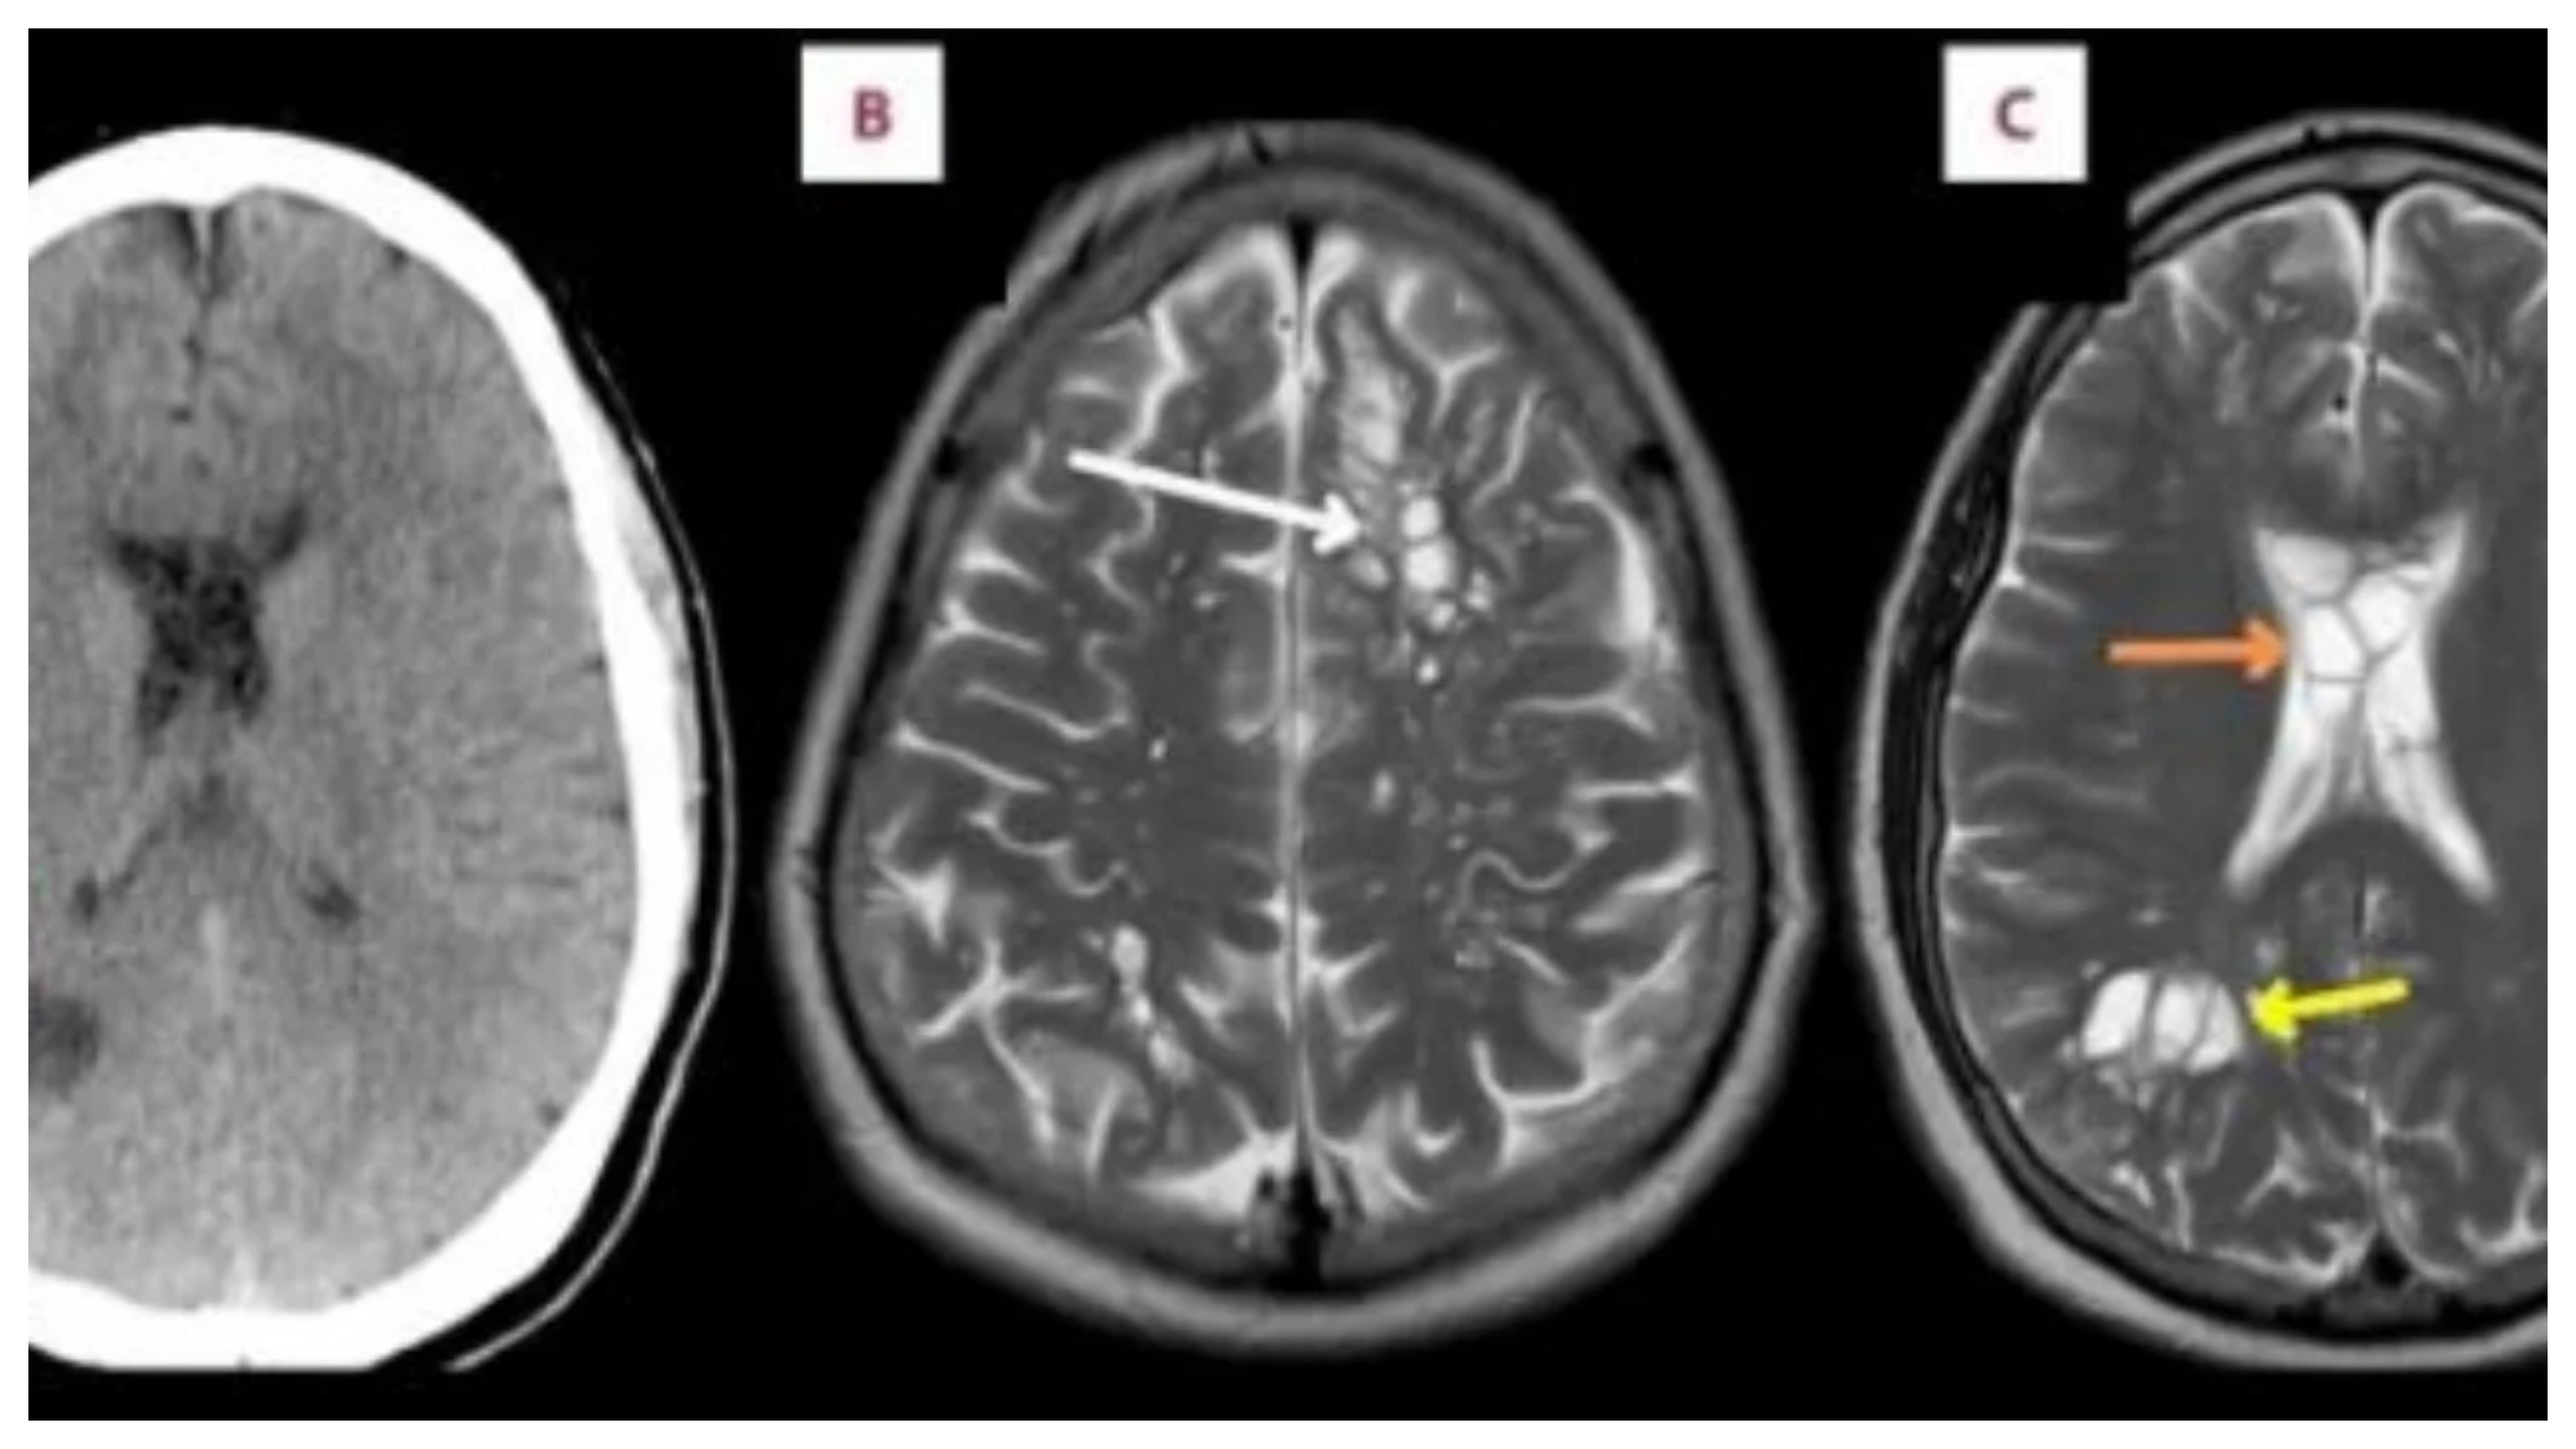

Një burrë në Florida që vuante nga migrena e vazhdueshme iu tha se kishte vezë krimbi në trurin e tij.Pacienti 52-vjeçar kërkoi ndihmë mjekësore pasi migrena e tij kronike u bë më e shpeshtë dhe ilaçet që përdorte për to nuk funksiononin më. Skanimet zbuluan ciste të shumta në të dy anët e trurit të tij që rezultuan të ishin vezë të krimbit shiriti i derrit. Vezët po i shkaktonin ënjtje nën kafkën e tij, e cila nga ana tjetër po çonte në migrenë të rregullt, sipas një raporti të shkruar nga mjekët e tij që u botua në American Journal of Case Reports.